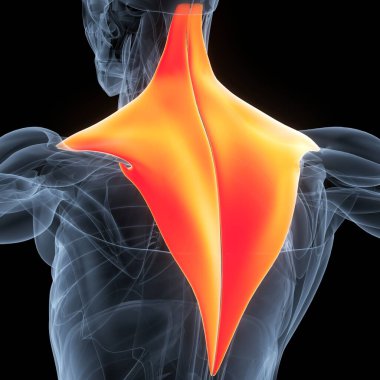

İnsan iskeleti anatomisi Scapula Kemiği Tıbbi Konsept için 3D Hazırlama

İskeletanatomiçene kemiğiyarım ayboyunlomberetmoidcapitateAltkısmınıHamate3d oluşturmaGöğüs kafesi3B illüstrasyoncarpalsağız sapımetakarplaralın kemiğiApendiküleruyluk kemiğioksipital kemikBurun kemiğikemiğigöğüs kemiğinin gövdesiayak kemikleriyarıçap kemiğiparietal kemikeksenel iskeletKalça kemiğilacrimal bonepalatine boneproximal phalangesinferior nasal conchaintermediate phalangesdistal phalangesclavicle bonekaval kemiğiBurun kıkırdağıkol kemiğikürek kemiğiBenzer İçerikler